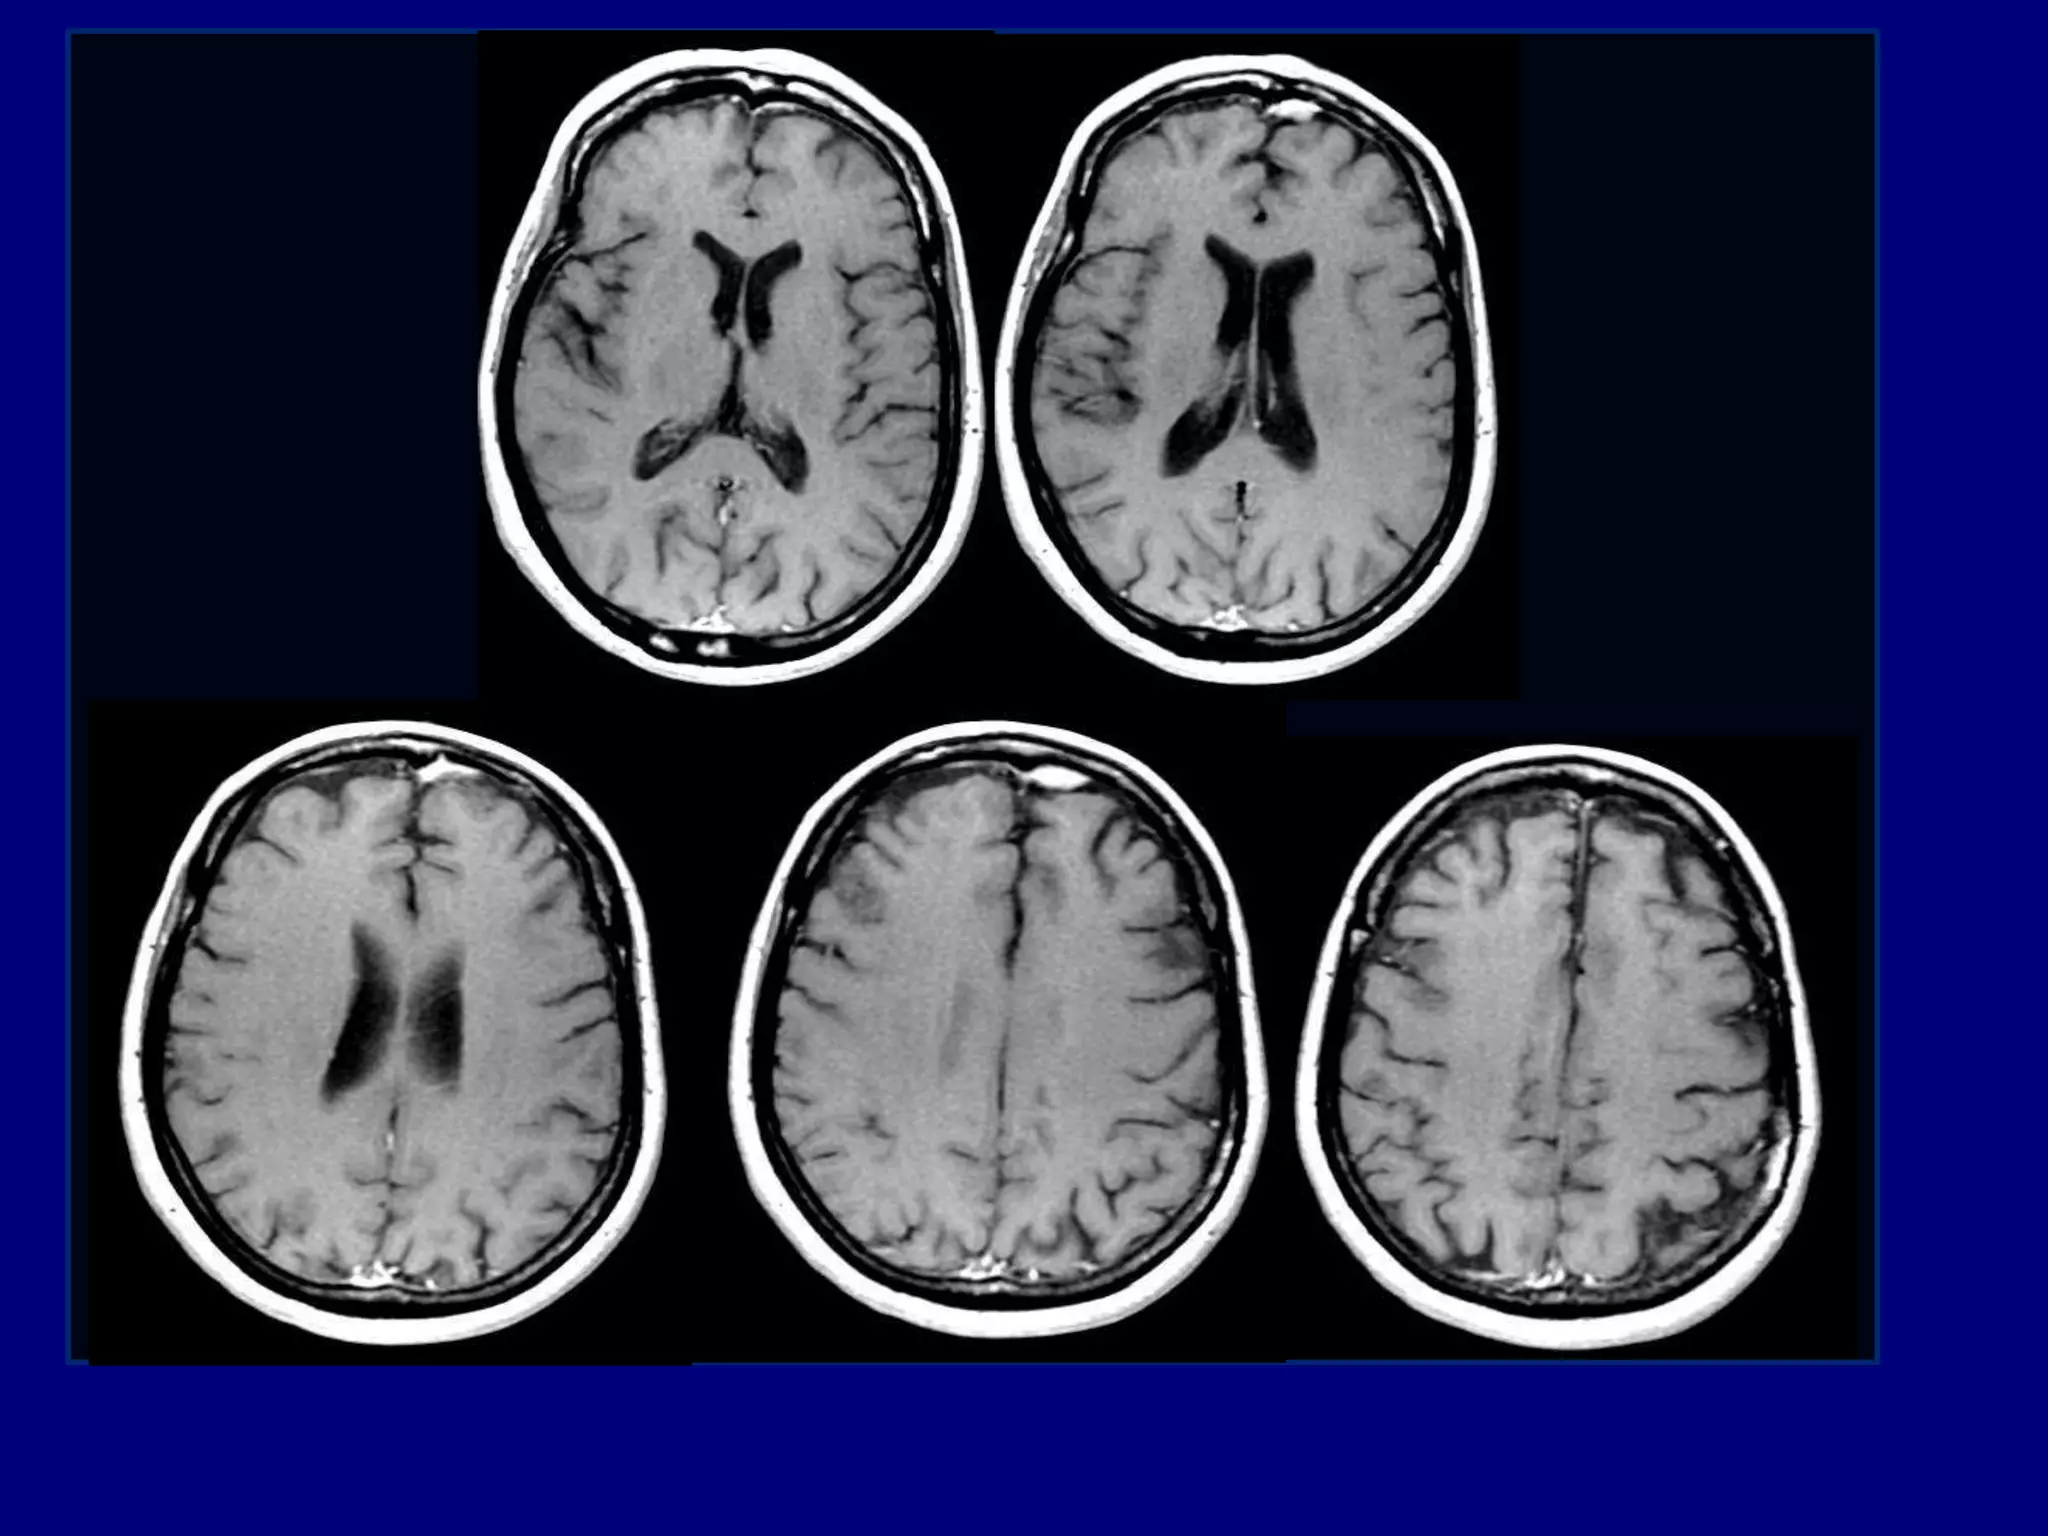

MRI 2012

T1-weighted post-gadolinium

MRI 2013